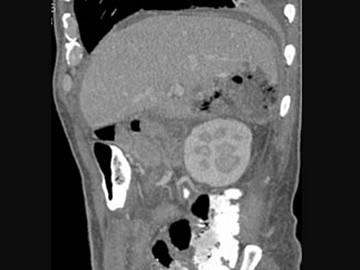

问题 男,44岁,发热、右上腹痛、压痛,右下肺呼吸音低,影像检查如图,最佳诊断是 ( )

选项 A.腹腔积液 B.膈下脓肿 C.肝包膜下出血 D.肝硬化腹水 E.肝癌

答案 B